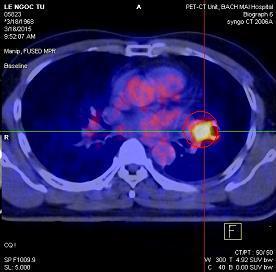

Ngày 28 tháng 10 năm 2014, bệnh nhân được chụp PET/CT cho thấy: Thùy trên phổi trái có khối tăng hấp thu F-18 FDG, kích thước 4,3x4,1x4,2cm, max SUV=8,9. Dịch màng phổi trái 0,7cm không tăng hấp thu F-18 FDG.

Hình 3. Hình ảnh chụp PET/CT: khối u phổi trái tăng hấp thu F-18 FDG kích thước 4,3x4,1x4,2cm (vòng tròn đỏ), tràn dịch màng phổi trái (mũi tên vàng, đã chọc tháo dịch màng phổi trái trước đó)

- Đốt sống C7 tăng hấp thu F-18 FDG, max SUV=3,6 (kích thước 1,2x1,3cm)

Hình 4. Hình ảnh PET/CT: tổn thương tăng hấp thu F18- FDG tại cột sống C7 nghĩ đến tổn thương thứ phát (vòng tròn đỏ)